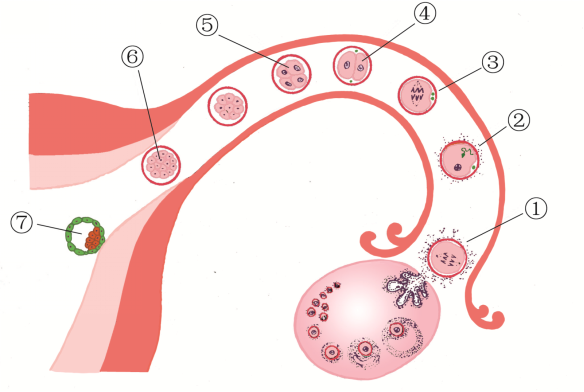

④2细胞期;⑤4细胞期;⑥8细胞期;⑦桑葚胚;⑧早期胚泡;⑨胚泡

排卵、受精与卵裂过程模式图

①排卵;②受精;③第一次卵裂;④2细胞;⑤4细胞;⑥桑椹胚;⑦胚泡